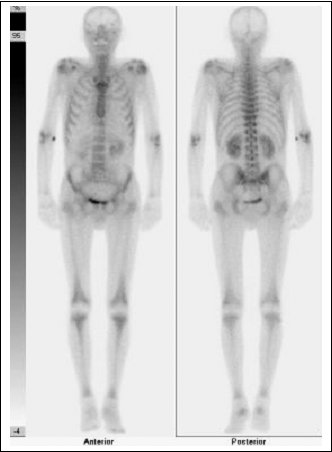

U tohoto pacienta byla indikována celotělová scintigrafie skeletu k vyloučení diseminace malobuněčného plicního karcinomu do skeletu z důvodu současně přítomného algického syndromu krční páteře.

Medical) byla za 2 hodiny provedena celotělová scintigrafie skeletu na dvoudetektorové kameře E.CAM firmy Siemens. Výsledkem vyšetření byl nález zvýšené osteoblastické aktivity patrné symetricky s maximem v okolí kolenních, ramenních a loketních kloubů a nad talokrurálními klouby. Nález odpovídal paraneoplastické hypertrofické osteoartopatii při malobuněčném plicním karcinomu.

/Obr. č. 1: Celotělová scintigrafie skeletu s nálezem paraneoplastické hypertrofické osteoartopatie patrné symetricky s maximem v okolí kolenních, ramenních a loketních kloubů a nad talokrurálními klouby. V pravé loketní jamce je patrné malé depo paravazálně aplikovaného radioindikátoru./

HOA spojená s periostální reakcí nejvíce patrnou na dlouhých kostech, lokalizovanou často v blízkosti kloubů a často symetricky, vede ke zvýšené akumulaci osteotropních radiofarmak, která je prokazatelná scintigraficky.